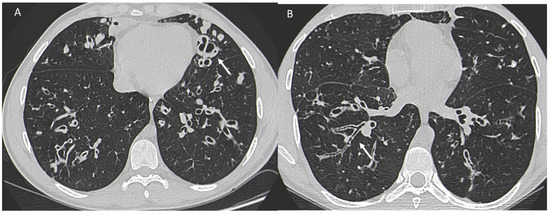

One study [103] investigated the survival of women with CF compared with men and showed that survival in the female population with CF is lower than that of men by about 5 years. Underlying this discrepancy is a different and higher anatomic-structural involvement on high-resolution chest CT (HRCT) in women with CF compared with men (Figure 3). Indeed, higher scores were recorded in women regarding the extent of bronchiectasis, involvement of bronchial branches, and severity of bronchiectasis, thus illustrating a virtually generalized involvement of the bronchial tree, as well as regarding air entrapment. This resulted in more frequent exacerbations, worse functional and nutritional outcomes, deterioration of quality of life, and greater structural damage in the female population.

Figure 3.

A woman and a man with CF with different and higher anatomo-structural involvement at HRCT in women with CF compared with men. (A) Diffuse cystic-varicoid bronchiectasis, with diffuse wall thickening and mucous plug (white arrow) in a young woman patient with cystic fibrosis. (B) Bronchiectasis with thickened walls (white arrow), especially in the medium-lower pulmonary lobes in a male patient with cystic fibrosis.

IPF is a chronic, irreversible, disabling disease with a fatal outcome characterized by a progressive decline in lung function. It is associated with a radiological pattern of usual interstitial pneumonia (UIP). In the literature, women have shown less fibrotic alterations than their male counterparts at HRTC (Figure 4).

Figure 4.

(A) Diffuse ground glass opacities with reticular thickening of the subpleural interstitium (white arrow), together with traction bronchiectasis in a case of pulmonary fibrosis with UIP pattern and smoking-related interstitial lung disease (ILD) in a female smoker. (B) A typical UIP pattern in a male smoker with idiopathic pulmonary fibrosis, together with diffuse ground glass opacities (white arrow) during an acute exacerbation.

A French multicenter prospective study [104] explored gender differences in an IPF cohort over a 5-year follow-up period. The cohort included 51 (22%) females and 185 (78%) males with a mean age at diagnosis of 70.1 ± 9.20 and 67.4 ± 10.9 years, respectively. At presentation, honeycombing and emphysema at HRCT were less common in females: (n = 40 (78.4%) vs. n = 167 (90.3%), p = 0.041) and (n = 6 (11.8%) vs. n = 48 (25.9%), p = 0.029), respectively. Fewer women than men also underwent transplantation during follow-up (n = 1 (1.96%) vs. n = 20 (10.8%), p = 0.039).